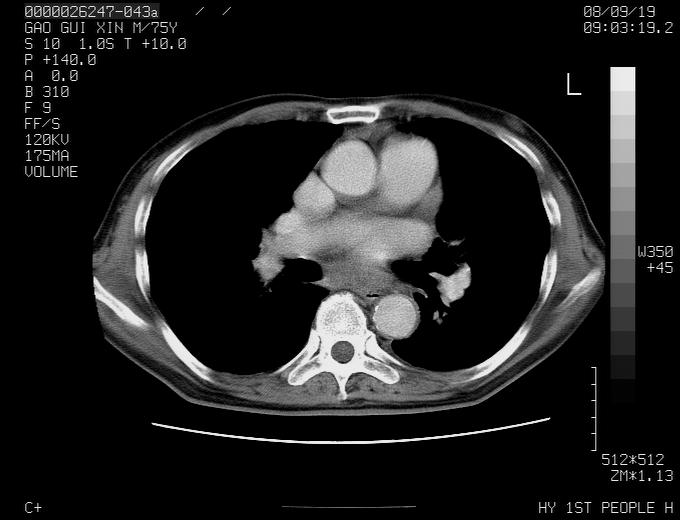

感谢各位老师的意见,左上肺病灶,我本人趋向结核,原因:左上肺见两个类圆形结节,仔细回顾4月份ct似乎原片在该处有条片状密度增高影,强化不明显。

现上传增强片,请各位老师仔细帮我看一下。

右上肺可见条索状影,并可见钙化,左上肺结节可以考虑为结核球,但气管前腔静脉后有肿大淋巴结,本人觉得左上肺结节不能排除转移瘤的可能,右上肺为陈旧性结核灶。

左肺上叶周围性肺癌并纵隔多组lnm.不可能是tb.

左肺上叶尖段瘢痕癌并纵隔淋巴结转移解释更好一些.

别再ct讨论了,一个纤支镜检查马上明确.肺癌不会错的!应该是低分化鳞癌.

1)左肺上叶尖段周围型肺癌并纵隔淋巴结转移。2)冠状动脉及主动脉钙化。

左上肺周围型肺癌并纵隔淋巴结转移。纤支镜检查